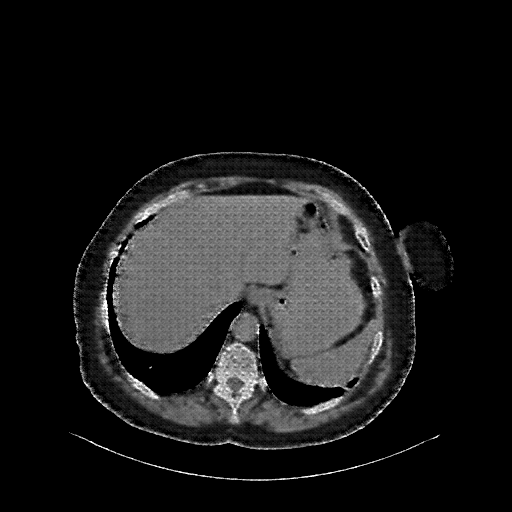

Reconstructed NATIVE CT scan (cycle consistency)

Full window (WL 1023.5, WW 4095 β†’ Low βˆ’1024, High +3071)

Lung window (WL -600, WW 1500 β†’ Low βˆ’1350, High +150)